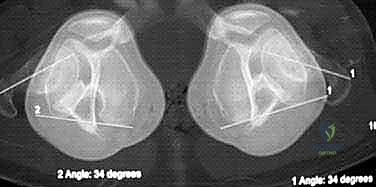

شكل 1 • أ. يعاني هذا الصبي البالغ من العمر 13 عاماً من السمنة والركبة الروحاء مجهولة السبب مع زيادة المسافة بين الكاحلين وعدم استقرار الرضفة. بدون تدخل جراحي دقيق لإعادة تنظيم الطرف، فإن التاريخ الطبيعي يشير إلى تدهور حتمي في وظيفة الركبة.

من الاكتشافات الشائعة التي يعالجها الدكتور هطيف بحرفية عالية هي عدم استقرار الرضفة (صابونة الركبة). الانحراف الميكانيكي للساق يؤدي إلى ارتخاء ثانوي في الأربطة، مما يجعل الصابونة عرضة للخلع الجزئي. الجميل في تقنية "النمو الموجه" أنها لا تصحح العظم فحسب، بل تحسن بشكل غير مباشر من استقرار الرضفة ومسار حركتها.

لا يكتمل التقييم السريري دون صور أشعة دقيقة. يطلب الدكتور هطيف صورة أشعة سينية طويلة للساقين بالكامل (من الورك إلى الكاحل) أثناء الوقوف (Standing Long-Leg X-rays). من خلال هذه الأشعة، يتم رسم خط المحور الميكانيكي، وحساب زوايا دقيقة جداً (مثل mLDFA و MPTA) لتحديد مركز التشوه بدقة متناهية، سواء كان في عظمة الفخذ، أو القصبة، أو كليهما.